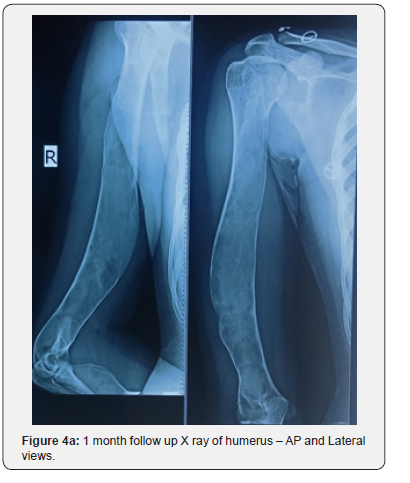

Then the patient was treated with oral risedronate 35 mg once weekly for 24 weeks, calcium and vitamin D3 combination tablets once daily for 6 months. The patient was reviewed every month with serial X rays (Figures 4a-4d) and serum calcium, phosphorus, alkaline phosphatase and vitamin D3 levels to monitor the response to treatment. The patient has been explained about the natural course, outcome and prognosis of the disease. Reassurance was given and the patient was discharged with the advice to retard heavy weight lifting and to perform daily routine activities with caution which will improve the functional quality of life.